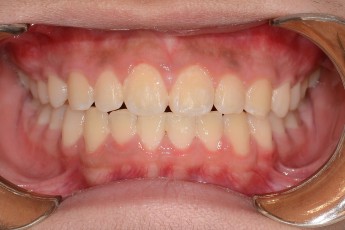

BEFORE & AFTER